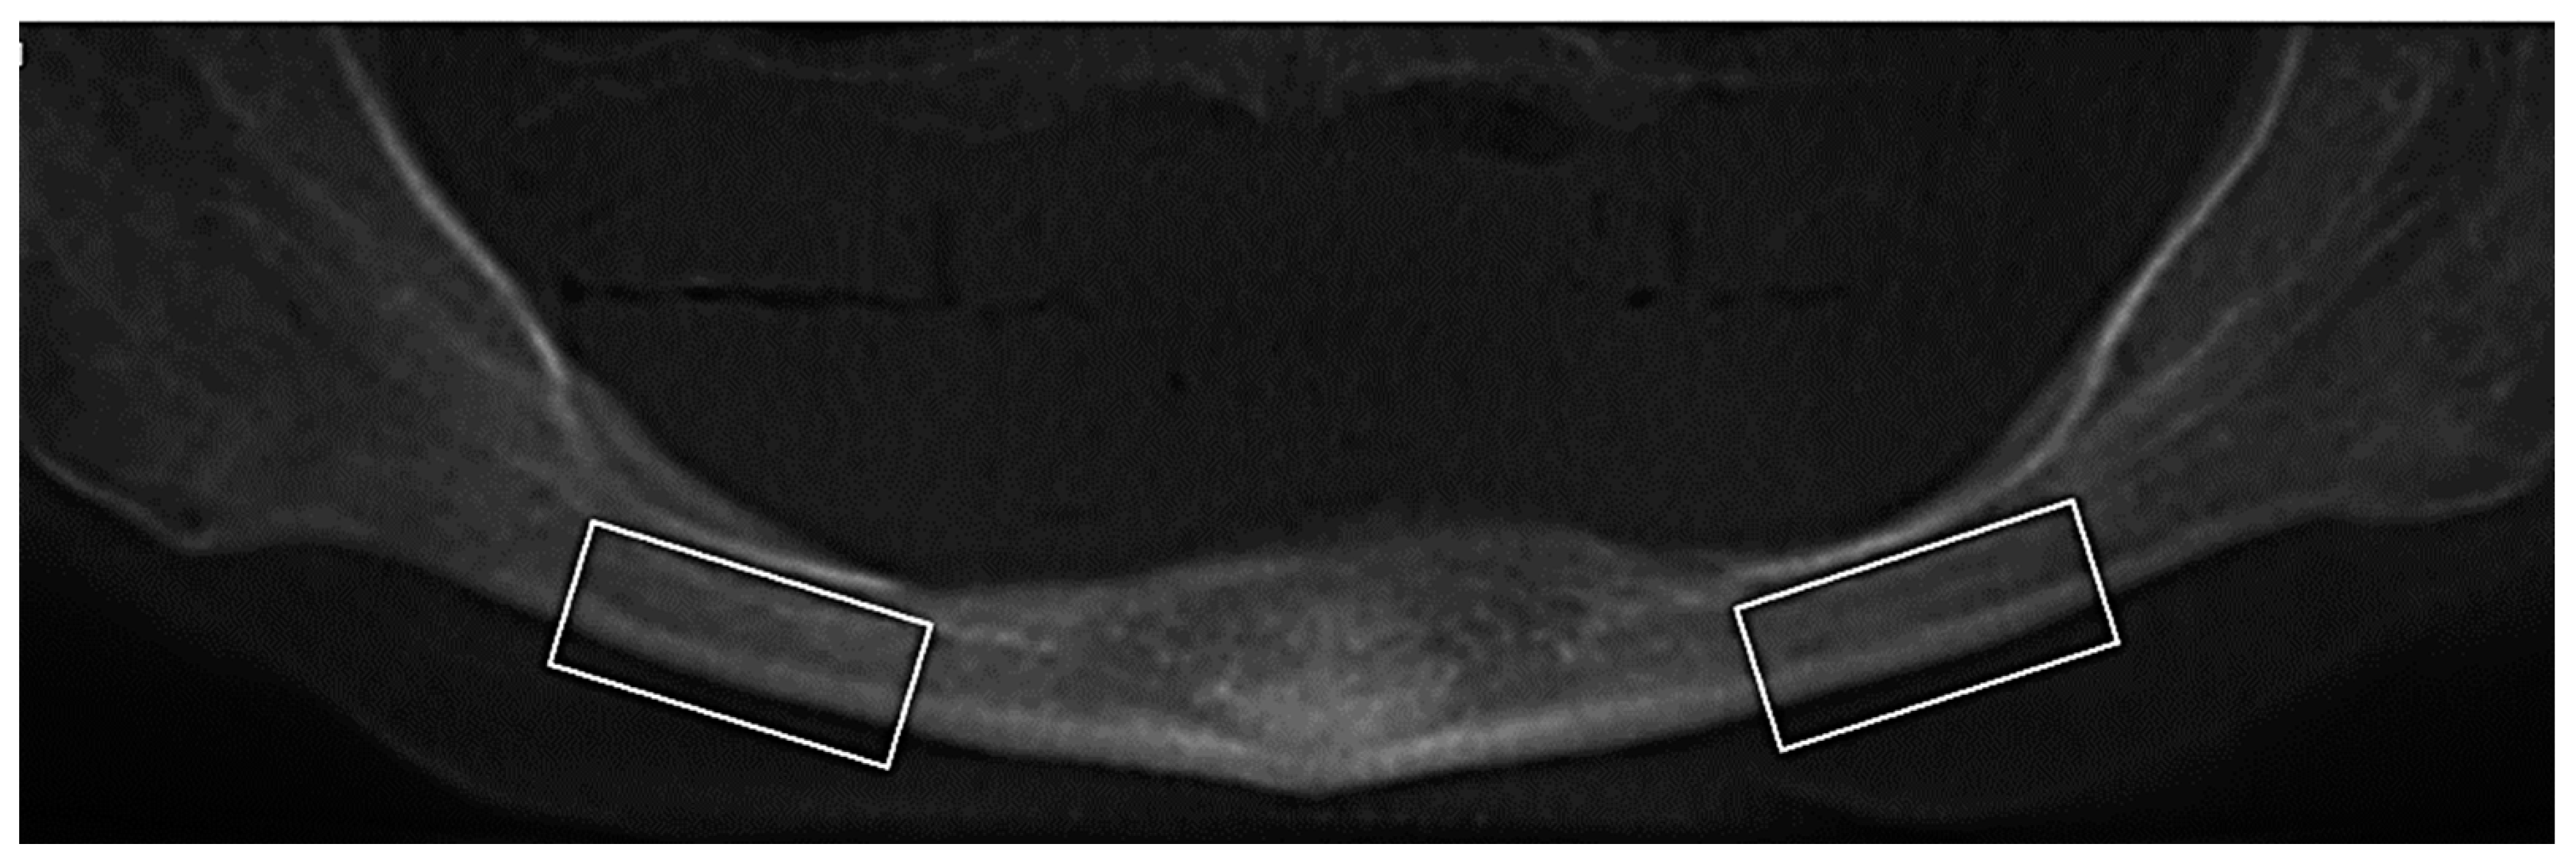

2.3.1. Trabecular and Cortical Bone Volume

2.3.2. Cortical Bone Thickness